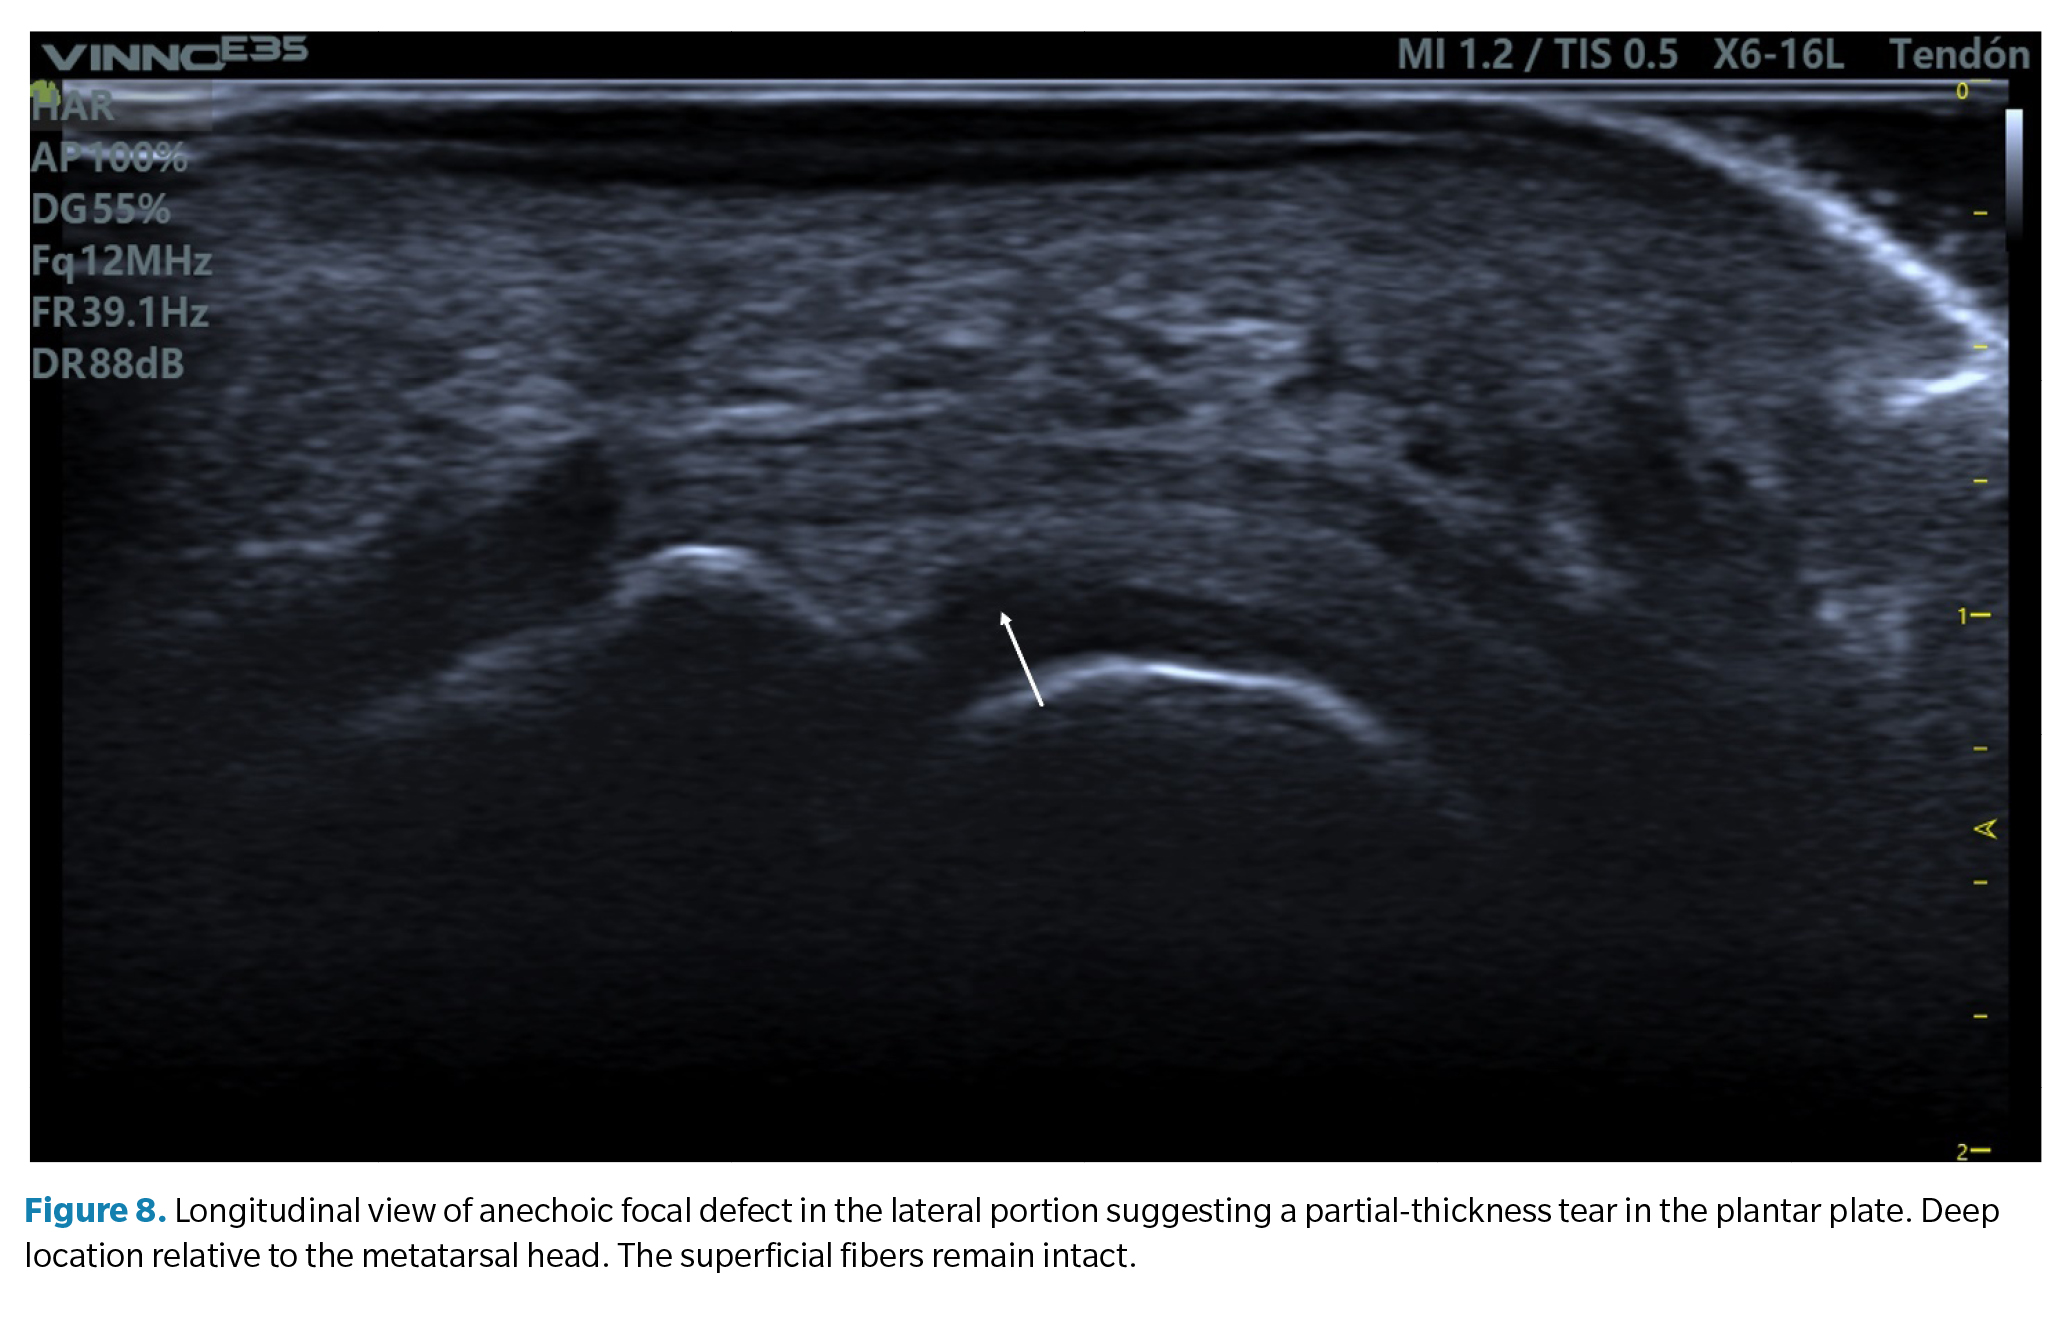

1. Anechoic or hypoechoic focal defect. They appear as a discrete cleft in the deep tissue area (the area that articulates with the metatarsal head) on its lateral margin. When the superficial fibers are intact, it is called a partial-thickness tear, while a tear that traverses the entire tissue to its superficial region is called a full-thickness tear(39) (Figure 8).